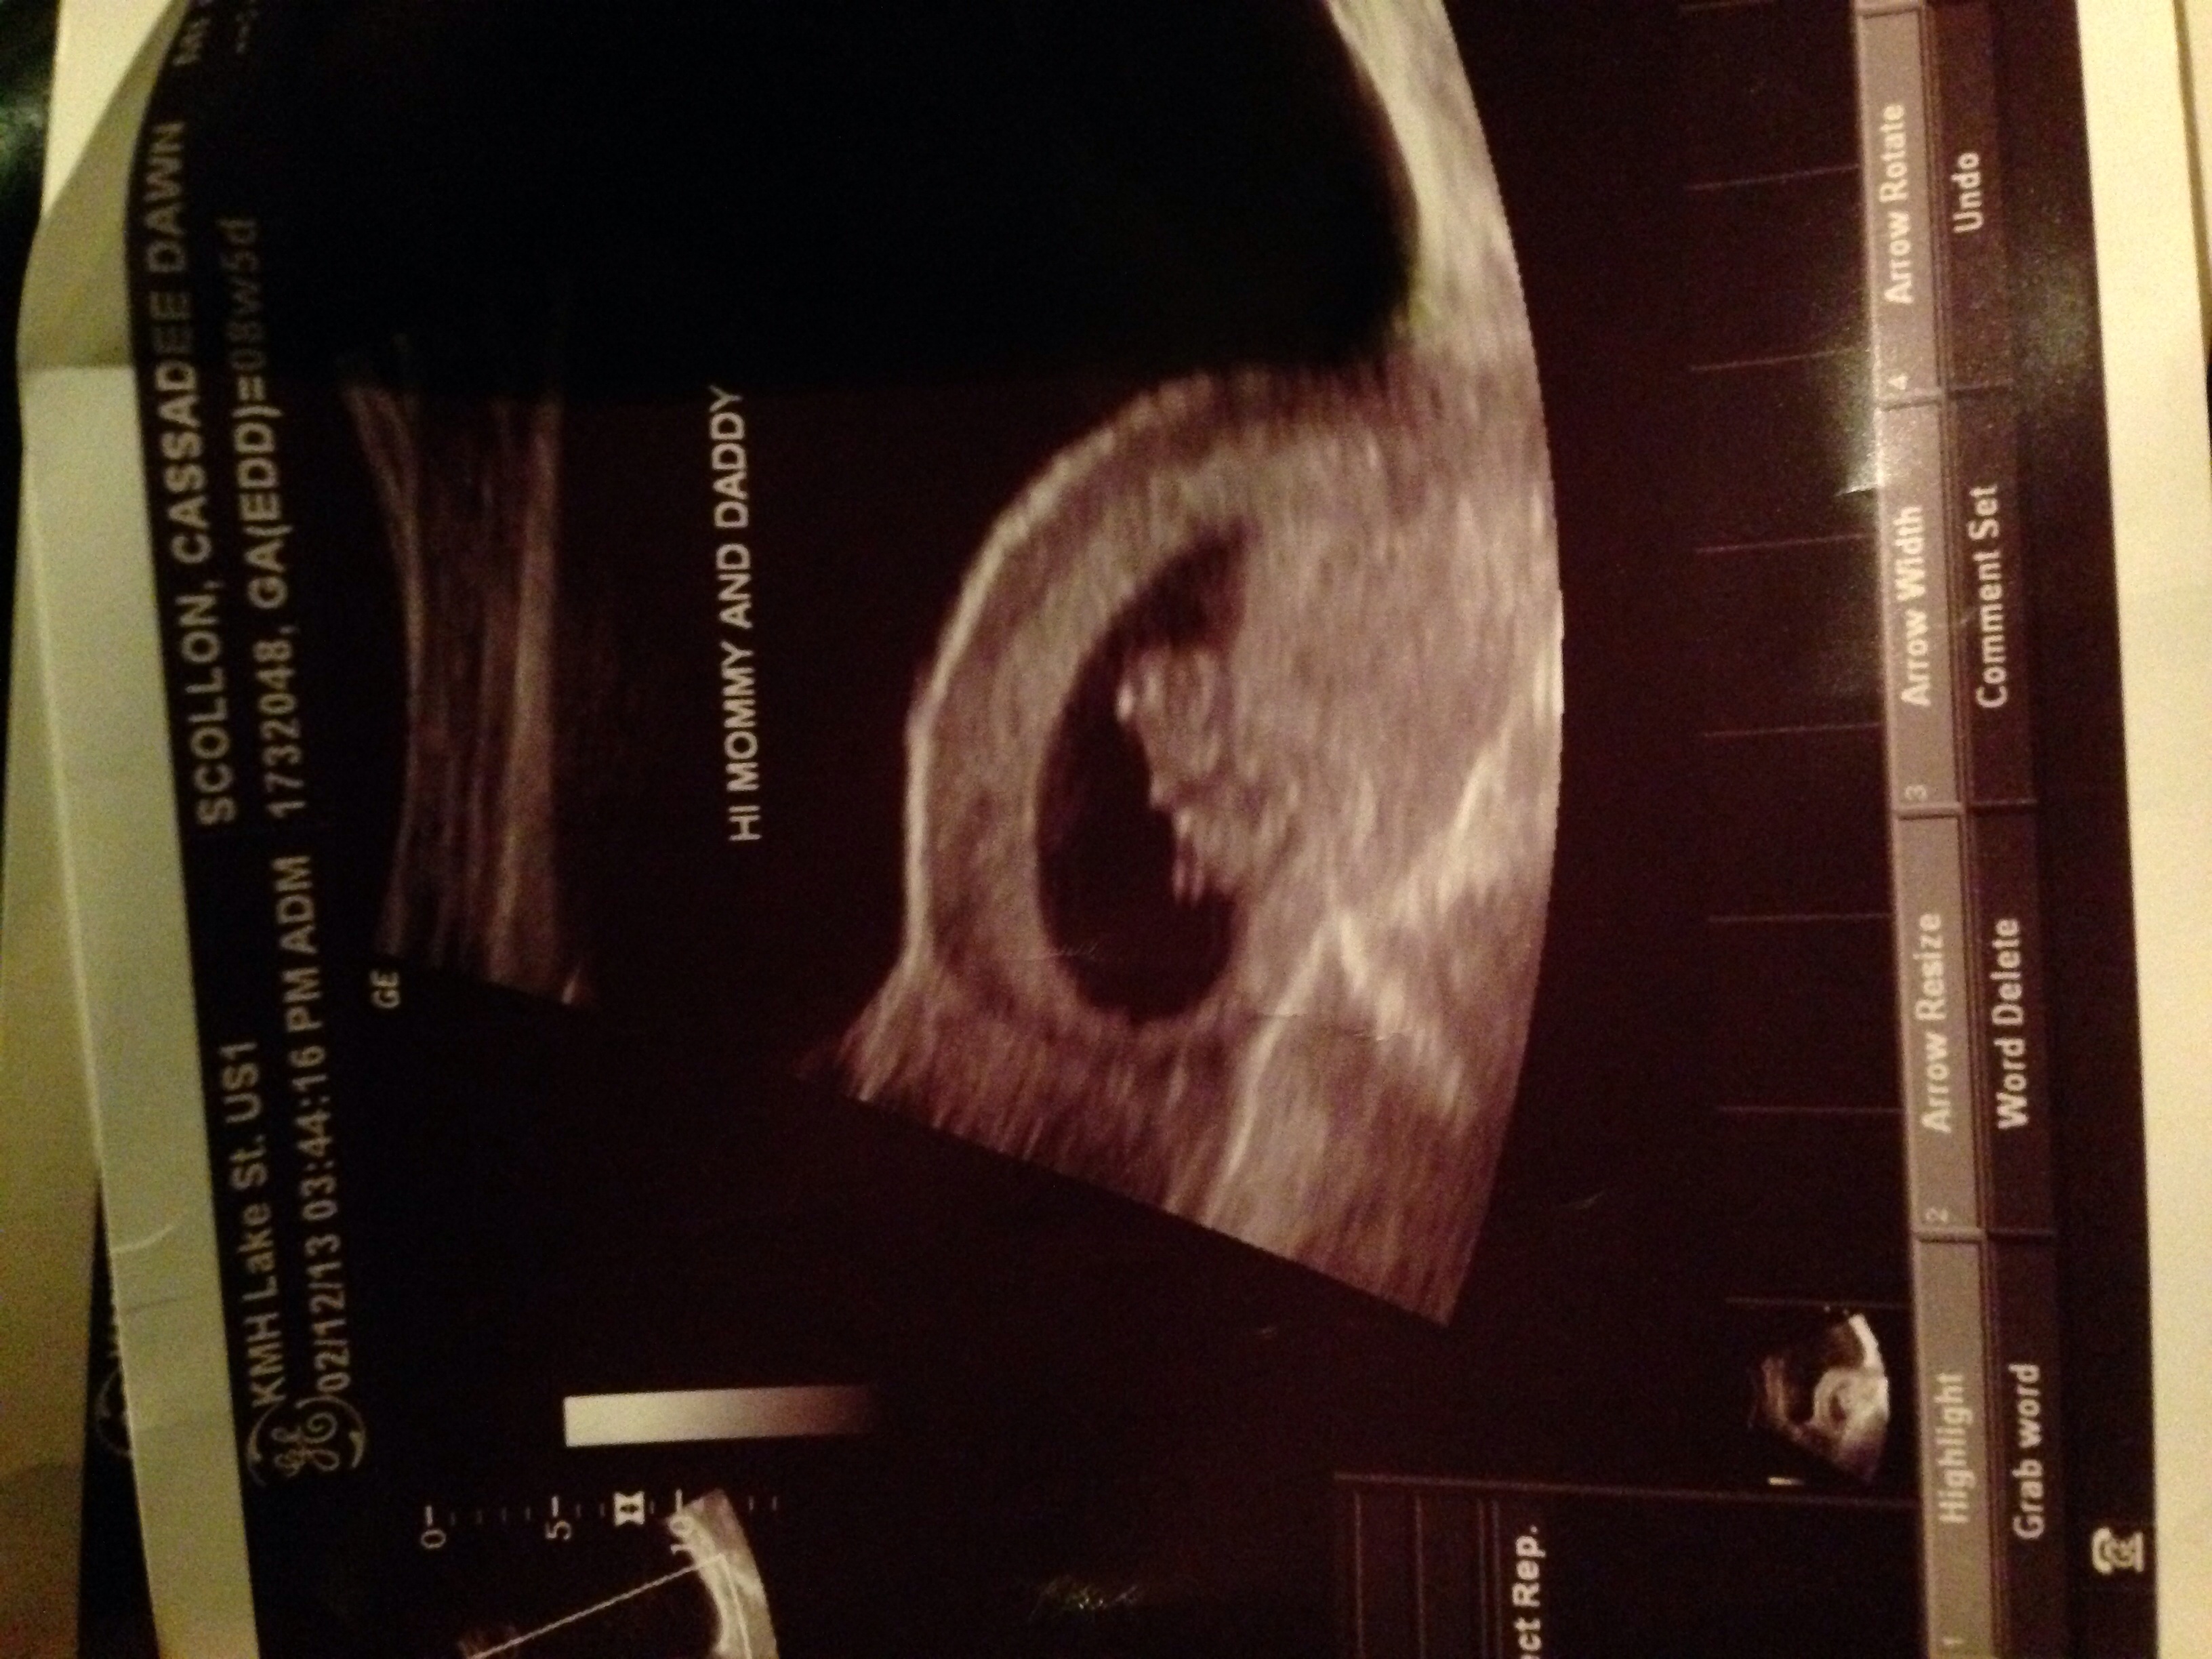

So I went to see my doc I am what I thought was 9 weeks she thinks I am 8 weeks 2 days. Baby at 6 weeks 6 days was measuring 4 mm and 119 bpm. Doc says that's small and slow. I am going for another US on Monday but doc said I am at a hight risk for a MC because the baby is small and has low hb...

Has anyone else had this I haven't been worries at all about MC until now.

Please pray for us cause this is our first pregnancy.